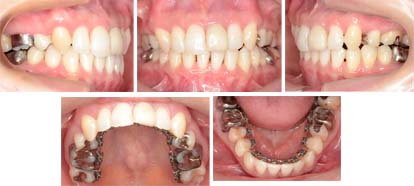

来院時の写真

気になっている点(主訴): 噛み合わせが深い出っ歯(上顎前突症)、下顎前歯部の叢生

噛み合わせが深く、出っ歯です。こういった場合は最初に下顎から治療を始めます。そして下顎の歯列が平坦になって排列してくると上顎にもリンガルブラケットが装着できるようになります。